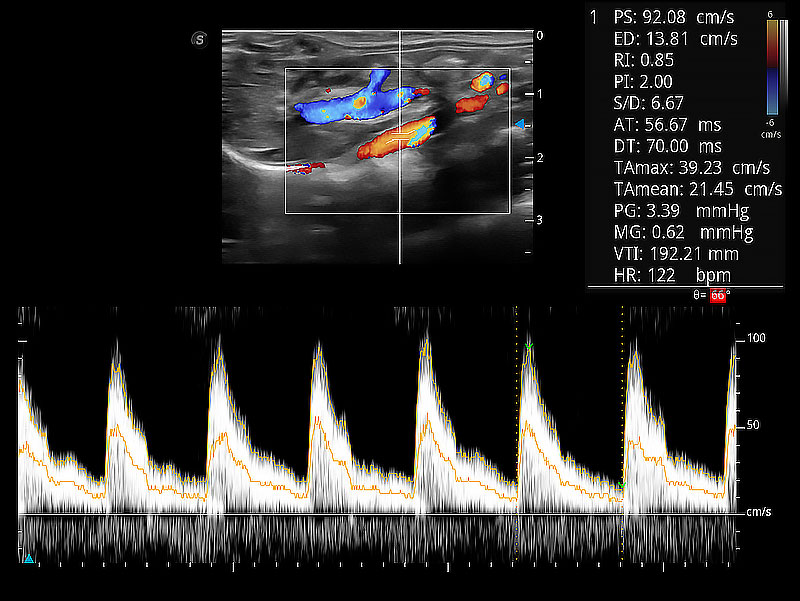

极大提升超低速微细血流的检出能力,同时更精准地滤除软组织和超声信号,为兽用医生提供以往无法通过常规血流获得的疾病诊断信息。